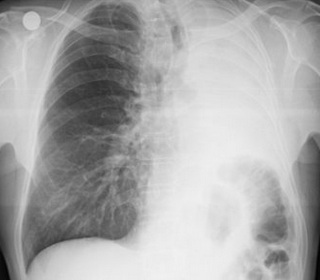

Rx toracică, incidență P-A

DESCRIERE:

la niv. întregului hemitorace drept → opacitate extinsă, nesistematizată, de intensitate mare, omogenă

caracter expansiv → împinge traheea și mediastinul de partea opusă

diafragm deplasat în jos

lărgirea spațiilor intercostale

umplerea spațiului costo-diafragmatic

DX: pleurezie masivă

DD: atelectazie → caracter retractil